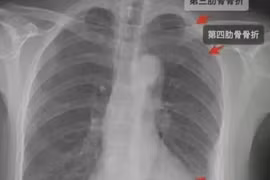

Một sản phụ đến BV ĐH Y dược Buôn Ma Thuột sinh mổ, người nhà tố bệnh viện có liên quan đến vụ gãy xương sườn của sản phụ. Lãnh đạo Sở Y tế Đắk Lắk đã yêu cầu thanh tra y tế vào cuộc.